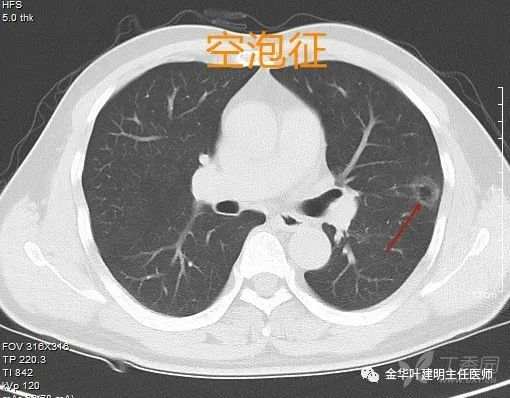

空泡征

空泡征:磨玻璃病灶伴有中间小空泡或空腔时,基本上都是恶性的,好像印象中基本上没有碰到良性的。如果空泡边上的成份密度较淡,则可能是不典型增生或原位腺癌,或密度较高,则会是微浸润或浸润性腺癌。